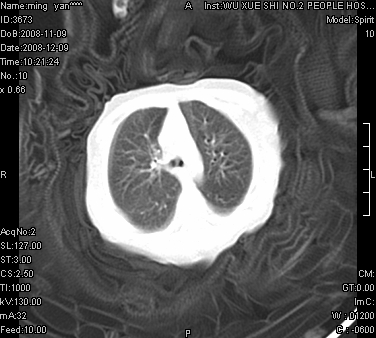

女.30天.咳嗽.喘3天.系三胞胎

考虑右肺下叶先天性肺囊肿,不除外合并右中叶肺发育不全

伴双肺感染

考虑右肺下叶先天性多发性肺囊肿可能。

考虑右肺下叶肺囊肿伴感染,右中叶节段实变或发育不全

这是一个先天性囊性腺瘤样畸形(congenital cystic adenomatid malformation,ccam),属于先天性肺发育异常,最近国外文献重新命名为先天性肺气道畸形(congenital pulmonary airway malformation,cpam),根据发生部位和畸形组织与气管、支气管的关系分成五型。本病以1岁以下婴儿多见,男性多于女性。病因为终末呼吸单元的异常增殖,形成多囊状结构。国内根据影响和病理表现分三型:ⅰ型为单个或多个大囊肿,直径大于2cm;ⅱ型为多个小囊肿,直径小于2cm;ⅲ型为大的非囊肿性病变,但显微镜下观察可见肿块由多发小囊组成(直径小于2mm)。本病可发生于肺内任何一部分,单侧肺占95%,中叶病变相对较少。